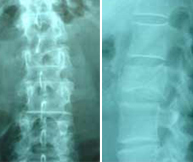

El Dr. Morgenstern realizando una Cifoplastia